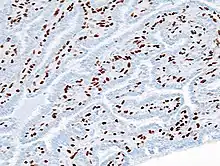

| Histopathology of intraductal papilloma of the breast by excisional biopsy. Immunostaining for p63 protein. | |